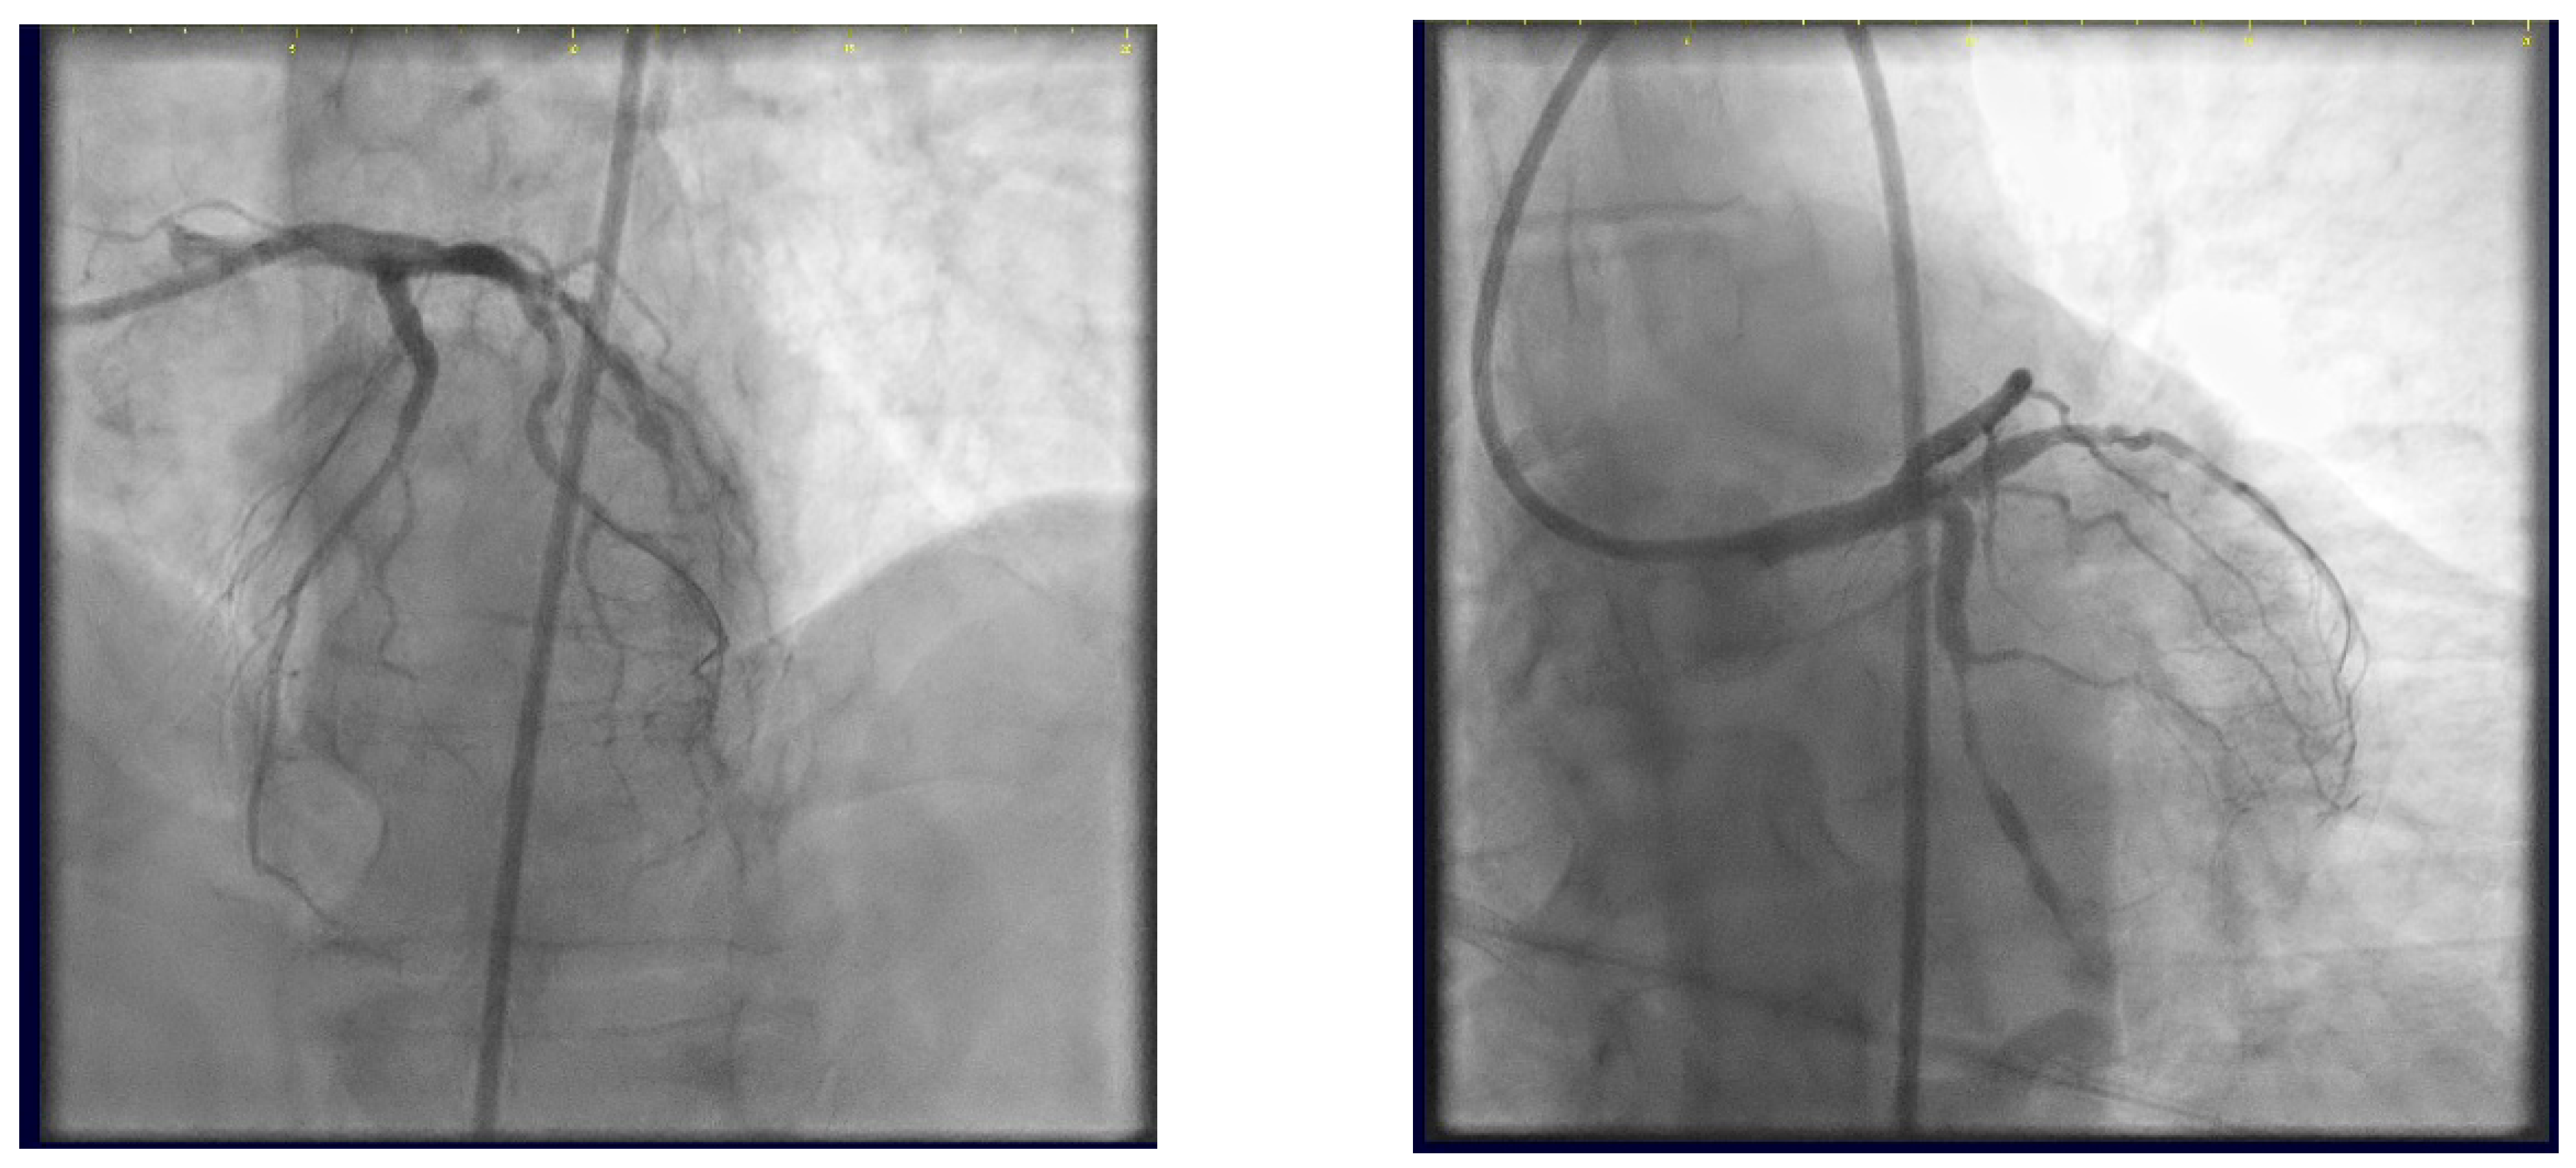

At the 6-month follow-up, the control angiography reveals patent stents at the trifurcation level (Figure 30).

Figure 30.

Control angiography at 6-month follow-up.

Our case report presents a successful proof of concept for a three-stent strategy in a high SYNTAX score patient. At 6 months post-procedure, the patient’s evolution was favourable, without the occurrence of cardiovascular events, the control angiography revealing patent stents.